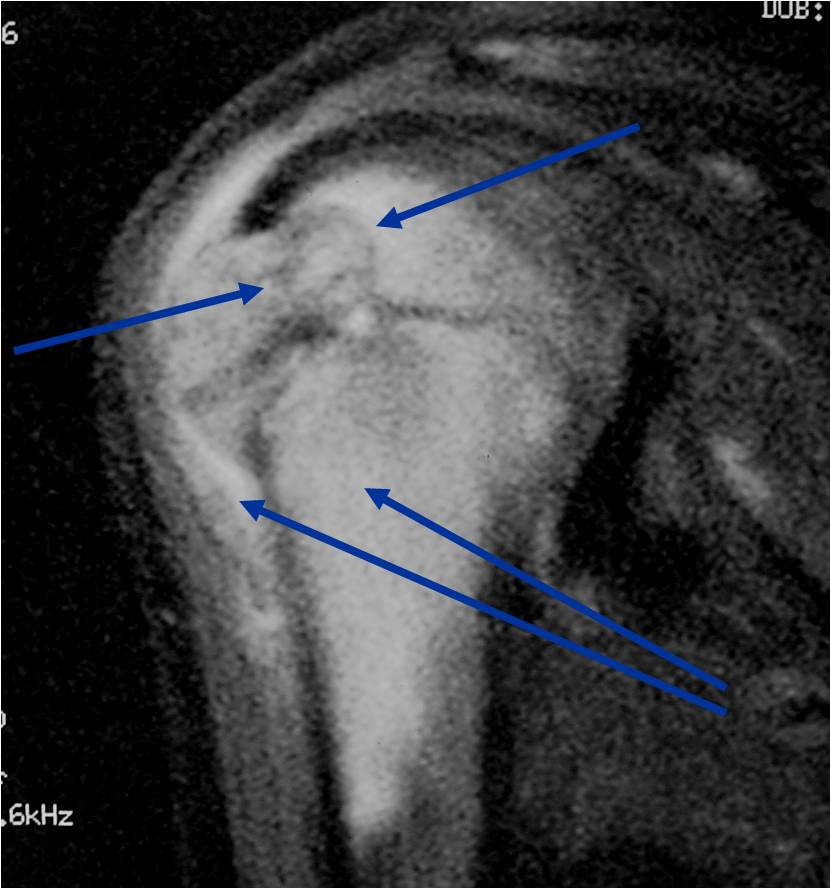

MRI appearance:

- Geographic, well circumscribed lesion in the epiphysis

- Intermediate Signal on T1

- High signal on T2 mixed with low signal areas (low signal areas proposed to be secondary to lysosomal content of highly cellular areas)

- Fluid/Fluid levels demonstrated in tumors that have undergone ABC change (aneurysmal bone cyst change)

- Extensive Surrounding edema is common

- Joint effusion in 30-50% of cases